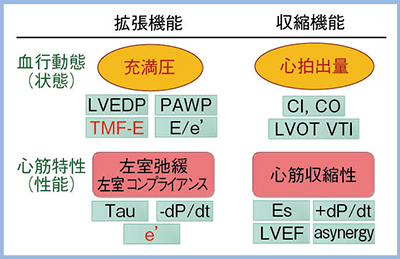

心エコーにおいて,充満圧は拡張機能,心拍出量は収縮機能を表しており,これらは血行動態(状態)の指標である。一方,心筋特性(性能)の観点から見ると,左室弛緩や左室コンプライアンスは拡張機能,心筋収縮の程度(心筋収縮性)は収縮機能を表している。拡張機能および収縮機能の評価におけるさまざまな指標を図1に示す。心エコーにおける血行動態指標のうち,僧帽弁口血流速波形の拡張早期波形E波(TMF-E)やE/e’は充満圧の指標であり,心拍出量はLVOTのVTIで評価できる。また,心筋特性である左室弛緩や左室コンプライアンスの指標はe’であり,LVEFやasynergyは心筋収縮性の指標となる。

図1 心不全の評価における心エコー指標

LVEDP:左室拡張末期圧,PAWP:肺動脈楔入圧,TMF-E:僧帽弁口血流速波形(TMF)の拡張早期波形(E波),E/e’:E波を僧帽弁輪運動速波形の拡張早期波(e’)で除した値,Tau(τ):減衰時定数,dP/dt:左室圧最大増加速度,CI:心拍出係数,CO:心拍出量,LVOT:左室流出路,VTI:速度時間積分値,Es:収縮末期,LVEF:左室駆出率,asynergy:壁運動異常